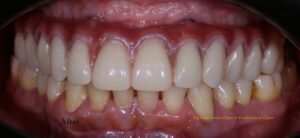

Upon his return six months later, we examined the implants and temporary denture, finding everything in excellent condition. We then proceeded with the fabrication of the final permanent hybrid denture prosthesis, which was completed within ten days. The result was highly satisfying and aesthetically pleasing. The patient left our Big Smile Dental Clinic & Prosthodontic Center extremely happy with the treatment and services he received.

Fig: Post-operative photograph after Permanent hybrid denture placement